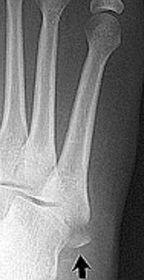

| What disease is this? What does the arrow indicate? | Rheumatoid arthritis. Arrow = Bone erosion secondary to inflammation of retrocalcaneal bursa. |

| What type of fracture is this? | Jones fracture - fracture of the diaphysis of the 5th metatarsal. More distal than an avulsion fracture. |